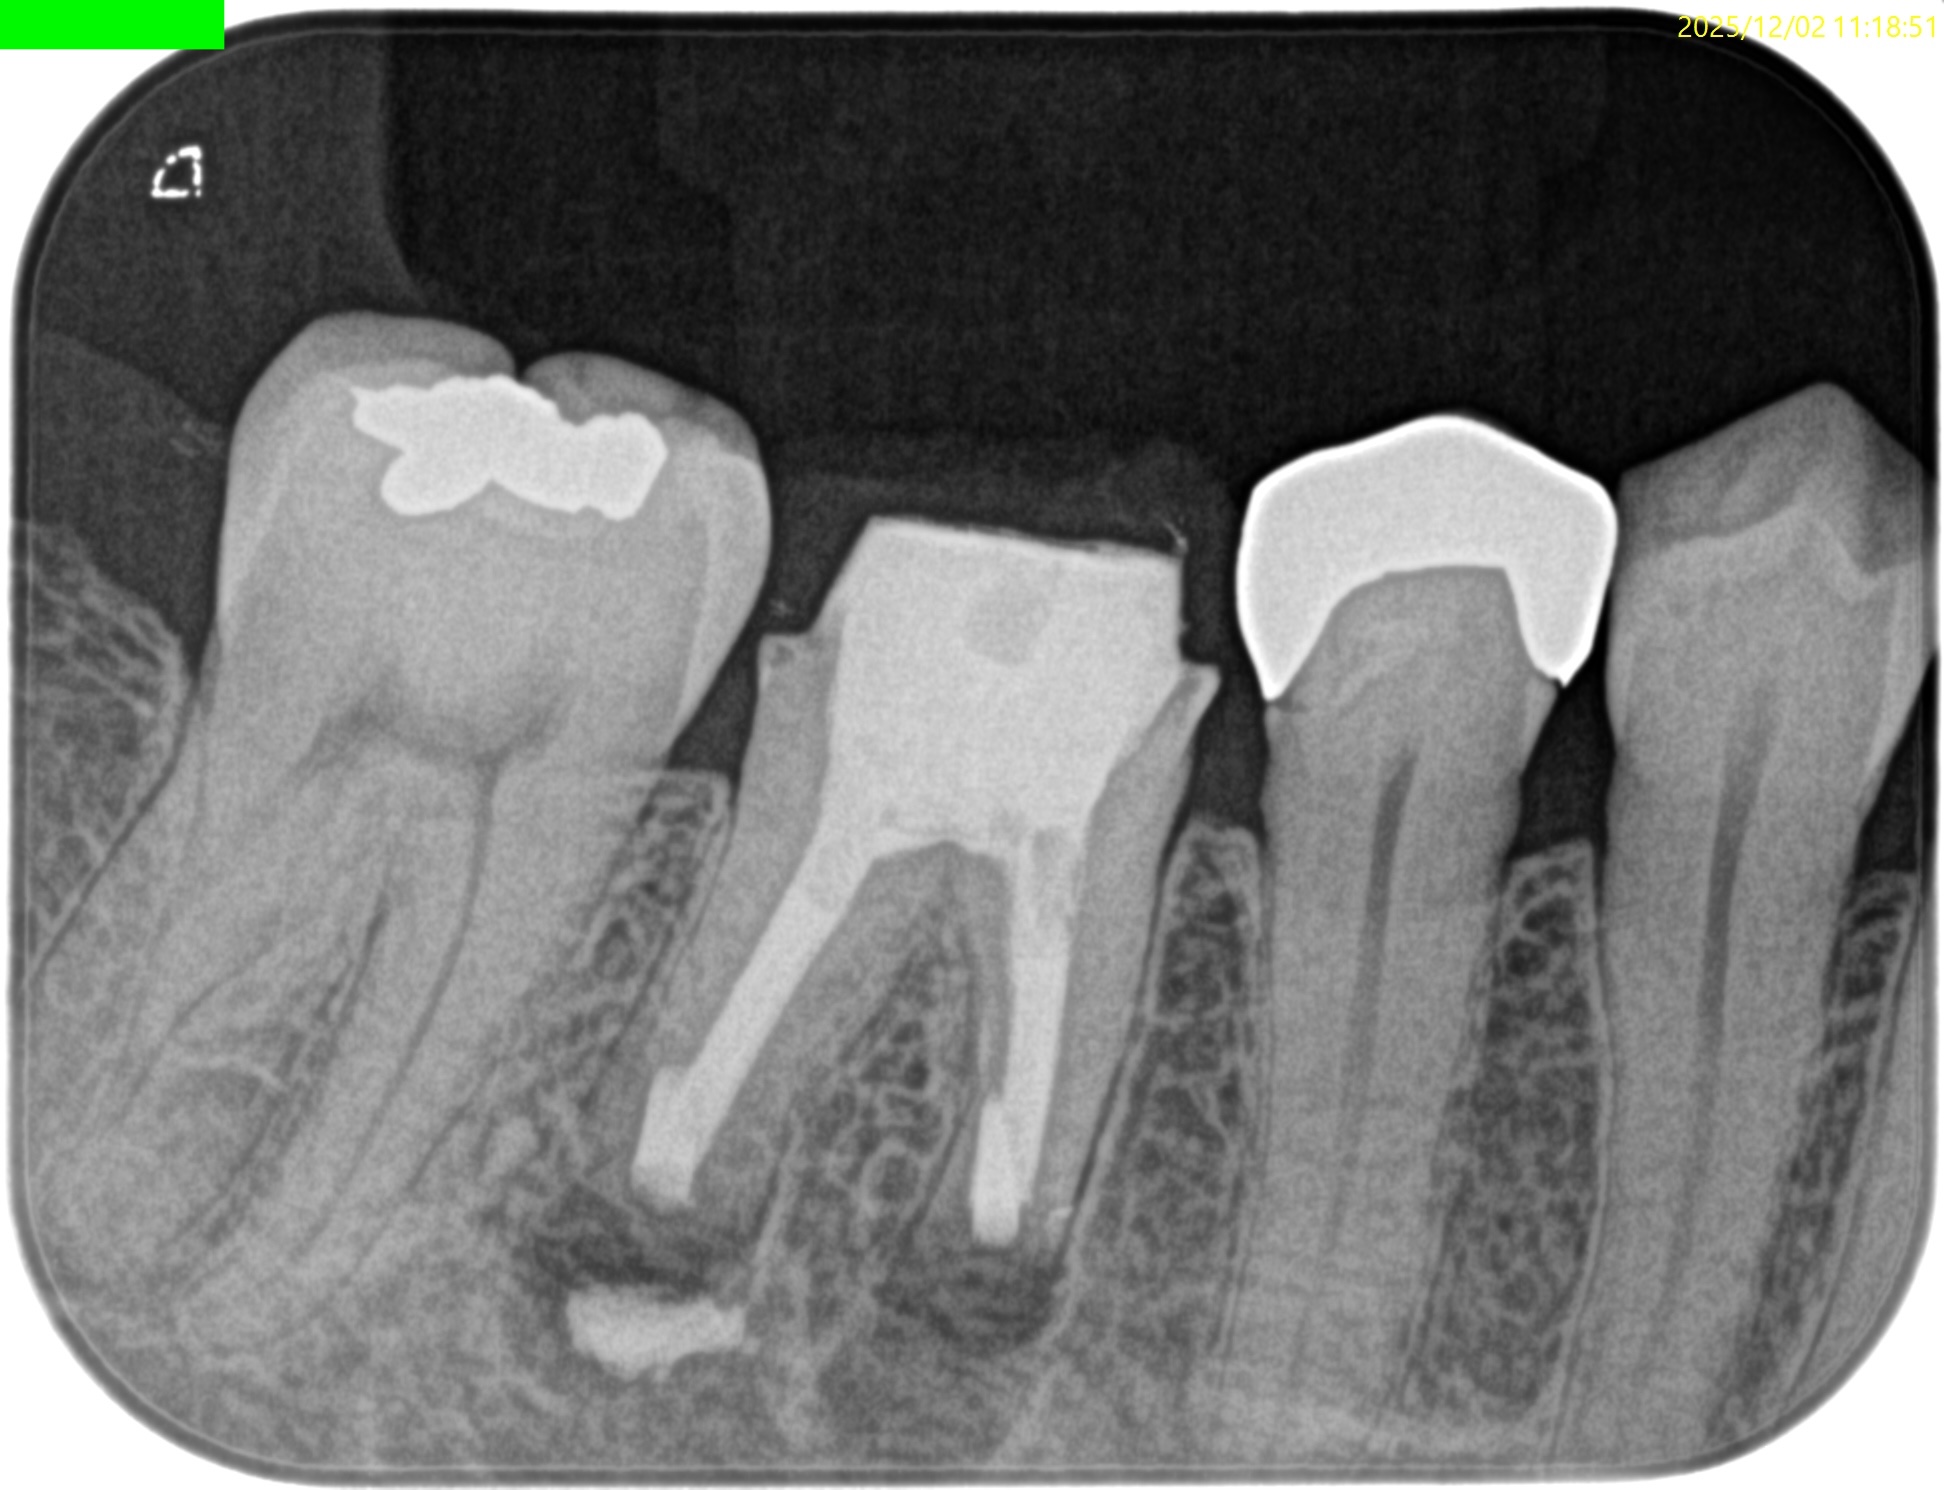

術後にPA, CBCTを撮影した。

#30 M,D Apicoectomy(2025.12.2)

縫合して終了した。

次回は1年後である。